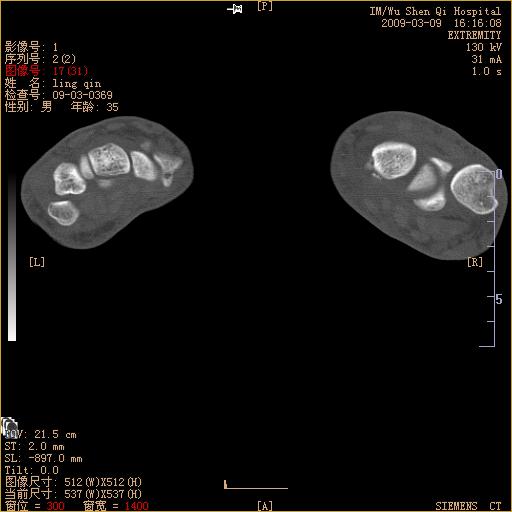

腕部有骨折、脱位,骨科面对ct片如何采取措施?三维一下。

请上传x线平片,腕骨多骨骨折

左侧舟骨及桡骨茎突骨折,第一掌骨基底部好像也有骨折,建议上传平片